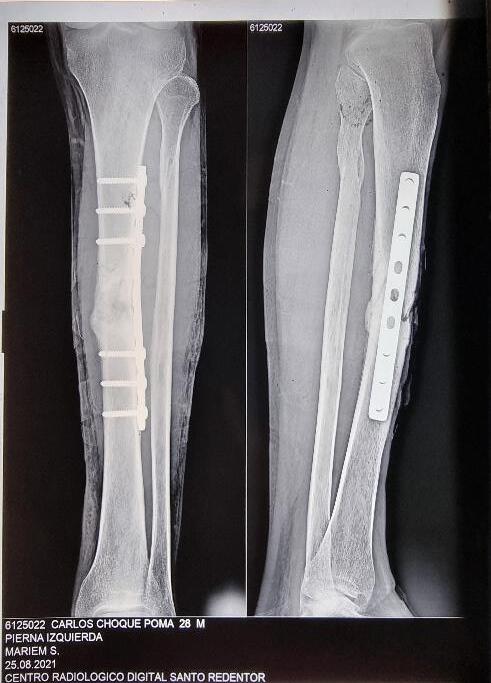

Uso de terapia de cierre asistido por vacío artesanal para el tratamiento de defecto de partes blandas en paciente postoperado de osteomielitis crónica en tibia

Use of artisanal vacuum-assisted closure therapy for the reatment of soft tissue defects in a postoperative patient with chronic tibial osteomyelitis

Eduardo Monasterios, Alvaro Mamani, Cristian Mostacedo